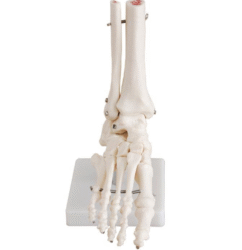

ATL-113 BONE MARROW PUNCTURE AND FEMORAL VENIPUNCTURE SIMULATOR SOFT

1) Simulate child leg, flexible joint, can place the suitable operating position

2) Anatomic landmark clearly, knee joint, patella, tibia, tibial tuberosity

3) Replaceable puncture skin, Injection module, simulated tibia and femoral vein vessel

4) Femoral pulse is touchable to locate operation position

5) Outflow of simulated fluid proves correct puncture position (tibia puncture/ femoral venous puncture).

Packing: 1pcs/carton, 77x28x22cm, 8kgs